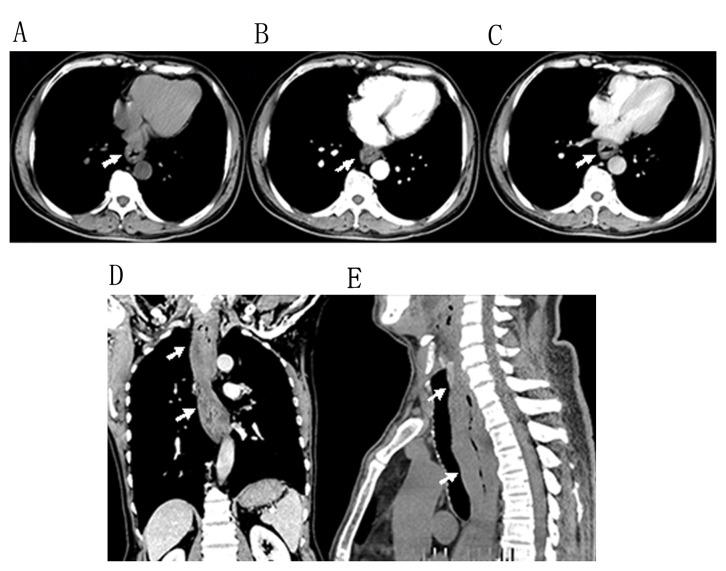

Primary esophageal natural killer (NK)/T-cell lymphoma is a markedly rare tumor. There were only 6 cases of the disease identified prior to June 2015. In the present study, the aforementioned cases were validated, and relevant computed tomography (CT) results and clinical features of primary esophageal NK/T-cell lymphoma were determined, to increase awareness of this type of tumor. CT features and clinical presentations of a patient with pathologically confirmed esophageal NK/T-cell lymphoma was analyzed. The patient exhibited non-specific clinical symptoms and CT images revealed diffuse thickening of the entire length of the esophagus. The patient received cycles of systemic chemotherapy and subsequent chest CT images demonstrated prompt and marked shrinkage of the tumor. At the time of writing, the patient has survived for 24 months and experiences a good quality of life without postprandial fullness or difficulty swallowing solid food. In addition, the characteristics of 6 patients with complete clinical features of this type of tumor, on the basis of a review of published studies (online PubMed, Medline, Google Scholar, Chinese Biomedicine Database and China Journal Full Text Database search), were retrospectively analyzed. Although primary esophageal NK/T-cell lymphoma is a markedly rare tumor, it is considered to be included in differential diagnosis of patients presenting with a fungal or viral infection, therapy-related mucositis or reflux esophagitis. The final diagnosis of primary esophageal NK/T-cell lymphoma is on the basis of a combination of clinical, CT and histopathological results.

原发性食管自然杀伤(NK)/T细胞淋巴瘤是一种极为罕见的肿瘤。在2015年6月之前仅确诊6例该疾病。在本研究中,对上述病例进行了验证,并确定了原发性食管NK/T细胞淋巴瘤的相关计算机断层扫描(CT)结果及临床特征,以提高对这类肿瘤的认识。分析了1例经病理证实的食管NK/T细胞淋巴瘤患者的CT特征及临床表现。该患者表现出非特异性临床症状,CT图像显示食管全长弥漫性增厚。患者接受了多周期全身化疗,随后的胸部CT图像显示肿瘤迅速且显著缩小。在撰写本文时,该患者已存活24个月,生活质量良好,无餐后饱胀感或吞咽固体食物困难。此外,在回顾已发表研究(通过在线检索PubMed、Medline、谷歌学术、中国生物医学数据库和中国期刊全文数据库)的基础上,对6例具有这类肿瘤完整临床特征的患者的特点进行了回顾性分析。虽然原发性食管NK/T细胞淋巴瘤是一种极为罕见的肿瘤,但在对表现为真菌或病毒感染、治疗相关的黏膜炎或反流性食管炎的患者进行鉴别诊断时应考虑该病。原发性食管NK/T细胞淋巴瘤的最终诊断基于临床、CT及组织病理学结果的综合判断。